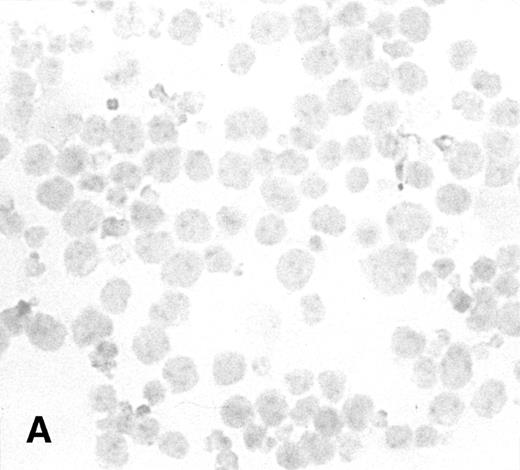

To determine the ability of an MuLV-based retroviral vector to stably infect NK cells, expression of IL-2 and Neo markers was evaluated. The efficiency of a flow-through method was determined by immunostaining for expression of the transgene. As a control, MFG-IRAP–infected NK-92 cells were used. Figure 1 shows staining for IL-2 of cultured P-NK-92 cells, which were negative for intracytoplasmic IL-2, and of transiently transduced NK-92 cells, which contained 10% to 20% stained cells. The percentage range of positive cells was determined by counting a total of 200 cells on each immunostained cytosmear prepared from three different cultures of transiently transduced NK-92 cells. These cultures were not tested by ELISA for the level of IL-2 in the supernatants because of the presence of exogenous IL-2. Instead, a culture of NK-92 cells transduced with the IRAP gene and containing 2% to 3% IRAP-positive cells by immunostaining (not shown) was tested in ELISA for the level of IRAP in the supernatant. At 72 hours posttransduction, the supernatant contained 8.4 ng IRAP/106 cells/48 h. P-NK-92 cells did not produce IRAP.

Immunostaining for IL-2 in transduced but nonselected NK-92 cells. (A) P-NK-92 cells incubated for 48 hours in the absence of exogenous IL-2 prior to staining. (B) Transduced nonselected (48 hours posttransduction) IL-2/Neo/NK-92 cells incubated for 48 hours in the absence of exogenous IL-2 prior to staining. Insert shows an IL-2–expressing NK cell (original magnification ×1,000). The staining reaction was developed with AEC, and the cells were counterstained with hematoxylin. For A and B, original magnification is ×500.